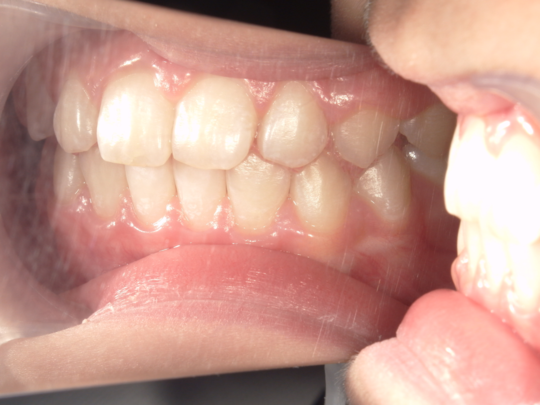

治療前

治療説明 歯科矯正で取り外し可能な矯正方法である床矯正で治療しました

治療期間 2年1か月

治療費200000 円

治療後

治療の副作用(リスク)歯の動き方には個人差があり、予想された治療期間が延長する可能性があります。。床矯正の使用状況、矯正歯科治療には患者さんの協力が必要であり、それらが治療結果や治療期間に影響します。2次矯正が必要になる場合もあります。